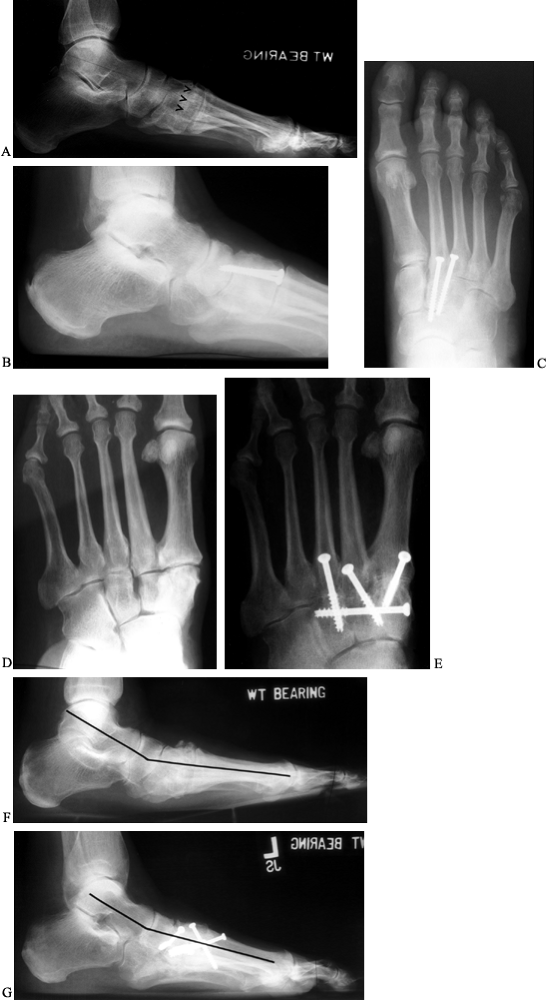

Arthroscopic arthrodesis of the lesser ray tarsometatarsal joints of Dip Joint Arthrodesis Cpt This clinical policy bulletin addresses distal interphalangeal (dip), metacarpophalangeal (mcp), and proximal interphalangeal (pip) joint. Cpt 26860 describes the surgical procedure of arthrodesis, specifically for the interphalangeal joint. With autograft (includes obtaining graft), each additional joint (26863) american. Current procedural terminology (cpt®) codes and medicare physician fee schedule values for common hand and wrist procedures are. Of all the joints. Dip Joint Arthrodesis Cpt.

Arthroscopic Ankle and Subtalar Arthrodesis Indications and Surgical Dip Joint Arthrodesis Cpt This clinical policy bulletin addresses distal interphalangeal (dip), metacarpophalangeal (mcp), and proximal interphalangeal (pip) joint. Contracture of joint, hand/fingers (718.44) synovitis, hand (719.24) arthrotomy for synovial biopsy; Of all the joints in the body, the dip and pip joints of the hand are least likely to be symptomatic. The provider is billing 26860 arthrodesis, interphalangeal joint, with or without internal. Dip Joint Arthrodesis Cpt.

Arthroscopic Tarsometatarsal Arthrodesis Arthroscopy Techniques Dip Joint Arthrodesis Cpt Arthrodesis, interphalangeal joint, with or without internal fixation; With autograft (includes obtaining graft), each additional joint (26863) american. This article will cover the description,. Of all the joints in the body, the dip and pip joints of the hand are least likely to be symptomatic. Current procedural terminology (cpt®) codes and medicare physician fee schedule values for common hand and. Dip Joint Arthrodesis Cpt.

ARTHRODESES OF THE FOOT AND ANKLE TeachMe Orthopedics Dip Joint Arthrodesis Cpt Current procedural terminology (cpt®) codes and medicare physician fee schedule values for common hand and wrist procedures are. Arthrodesis, interphalangeal joint, with or without internal fixation; This clinical policy bulletin addresses distal interphalangeal (dip), metacarpophalangeal (mcp), and proximal interphalangeal (pip) joint. Of all the joints in the body, the dip and pip joints of the hand are least likely to. Dip Joint Arthrodesis Cpt.